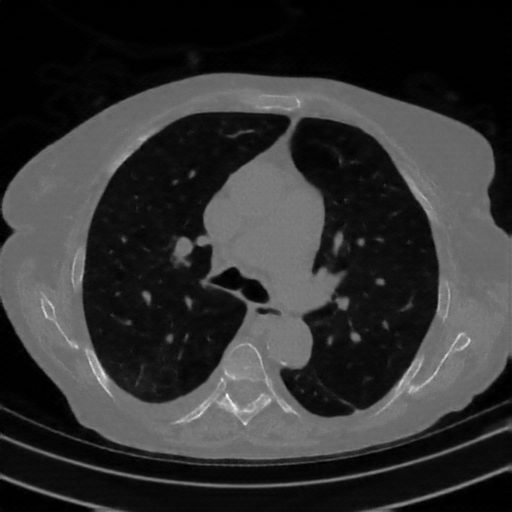

Generated VENOUS CT scan (A→B translation)

Full window (WL 1023.5, WW 4095 β†’ Low βˆ’1024, High +3071)

Actual HU range: [-1024.0, 1137.2]

Lung window (WL -600, WW 1500 β†’ Low βˆ’1350, High +150)

Actual HU range: [-1201.8, 150.0]

Mediastinum window (WL 40, WW 400 β†’ Low βˆ’160, High +240)

Actual HU range: [-160.0, 240.0]